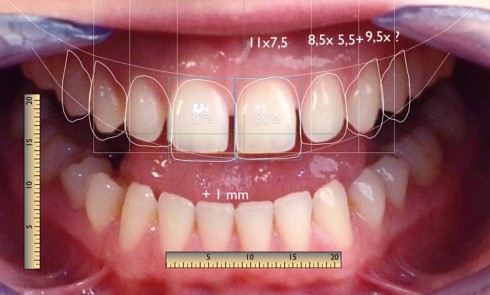

Article réservé à nos abonnés Analyse diagnostique d’un traitement esthétique : Digital Smile Design®

Le Digital Smile Design® vient compléter les outils classiques en rationalisant et en objectivant les différents éléments de la composition...